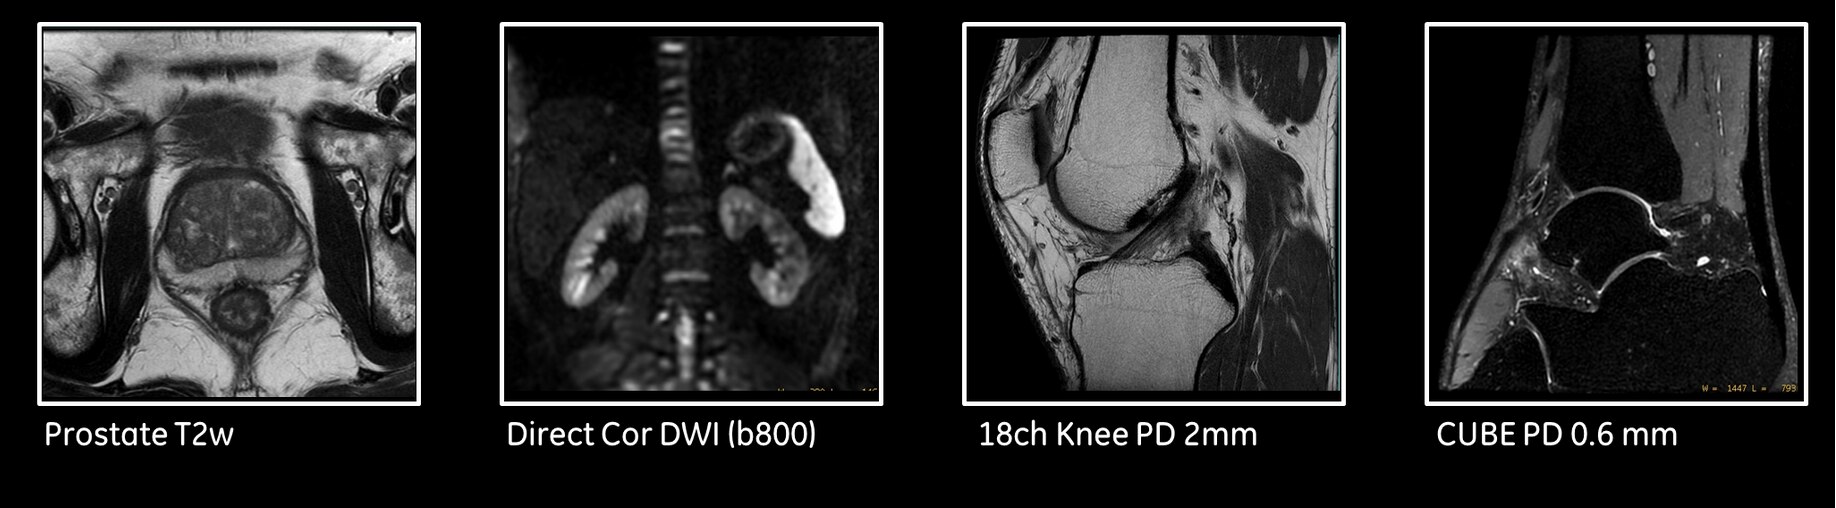

Breathe Free

With its free-breathing imaging applications and advanced motion correction software, SIGNA Pioneer will compensate for patient movement and allow complete free-breathing body imaging. This includes dynamic contrast enhanced MR imaging, improving dramatically

patient experience but also image quality in very challenging situations.